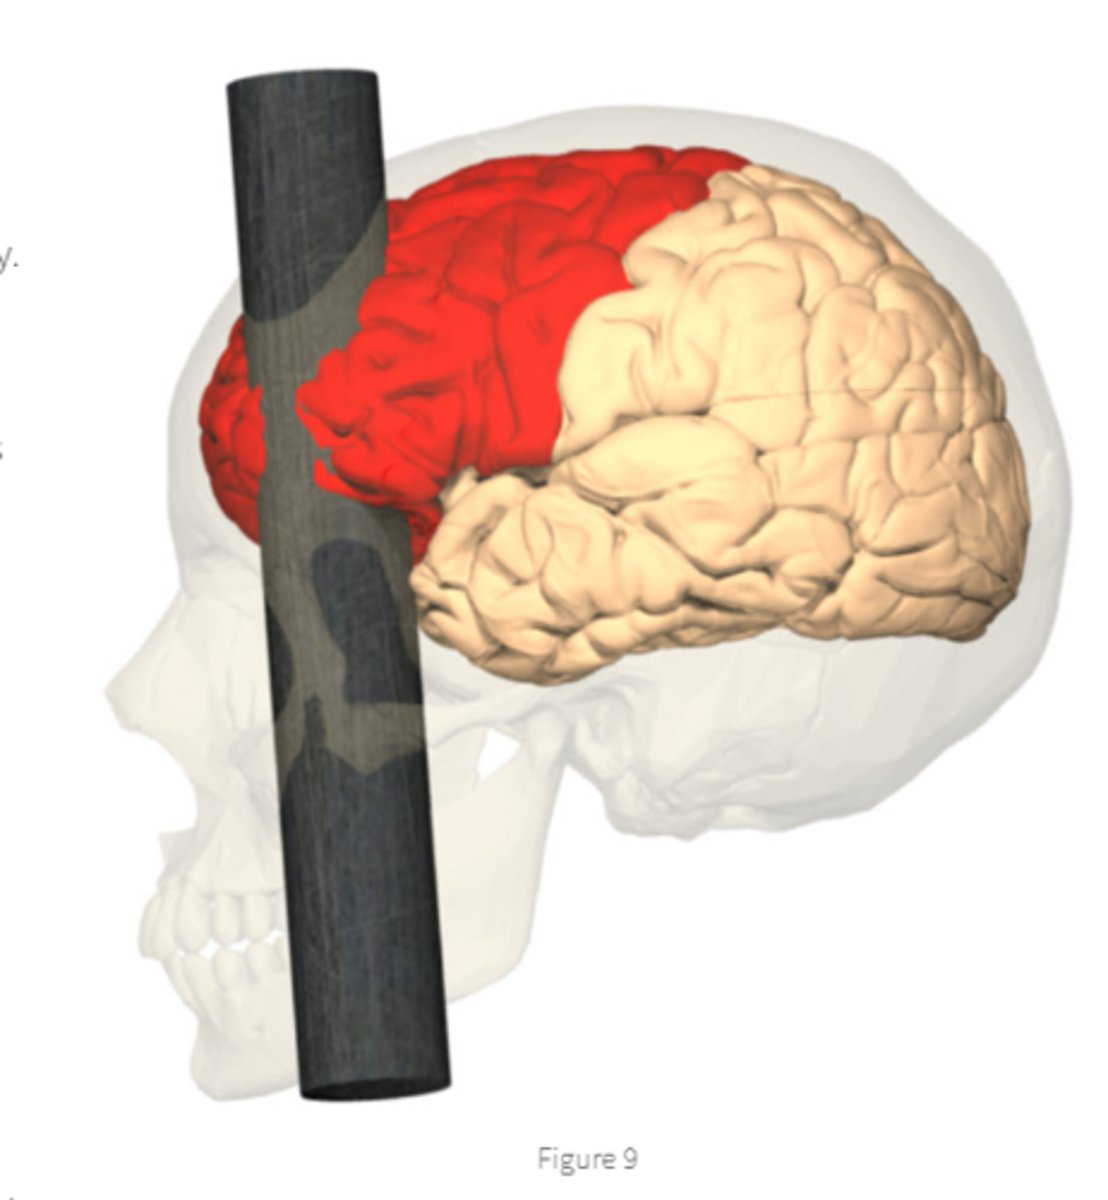

Phineas Gage

destroyed frontal cortex bilaterally,

unrestrained in trying to satisfy his drives

who is this? what damage sustained?

how behavior changed?